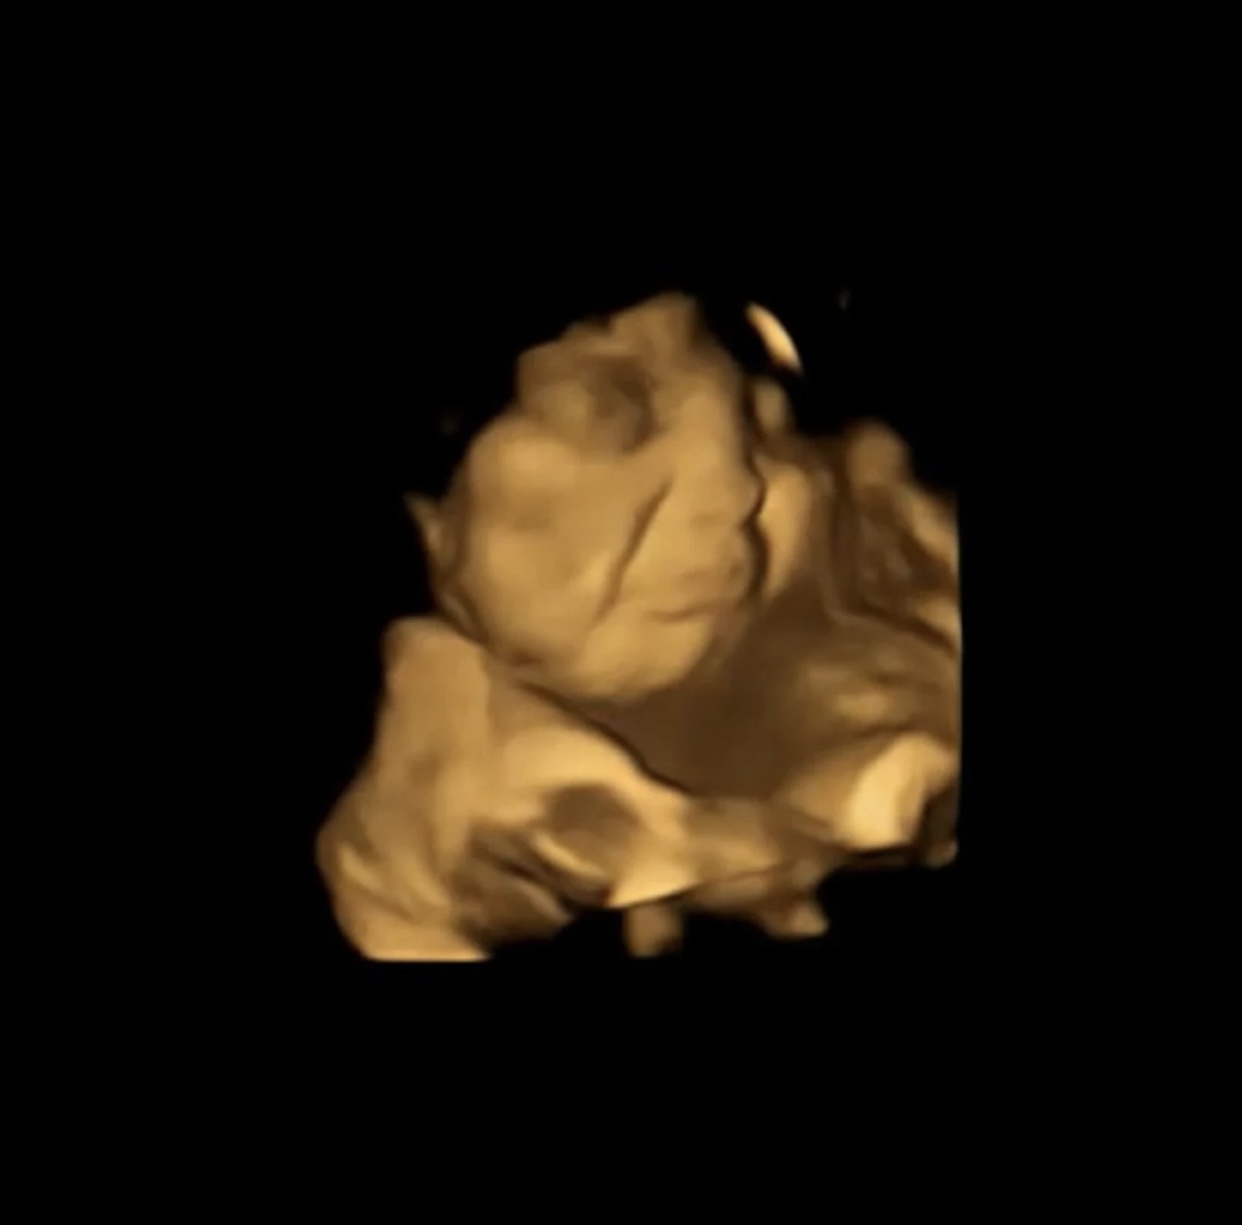

che do dinh duong anh 1

Một hình ảnh từ nghiên cứu FETAP (sở thích mùi vị của thai nhi) cho thấy phản ứng của thai nhi với cà rốt ở bên trái, so với một khuôn mặt trung lập ở bên phải. Ảnh: DurhamUniversity.